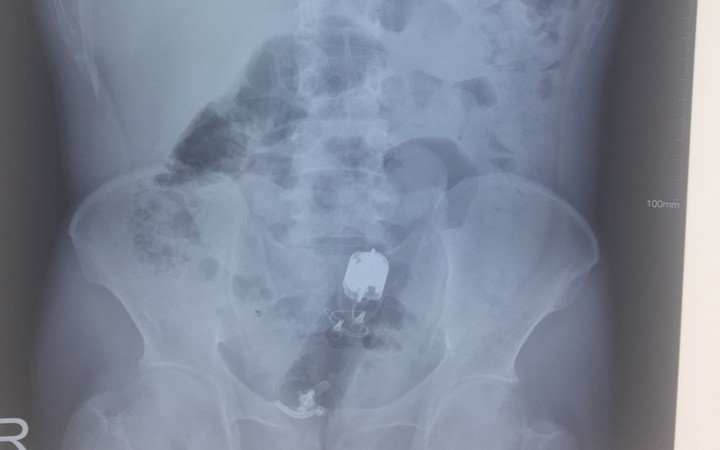

Khi chảy máu thấp mức độ nặng, có dị vật trực tràng.